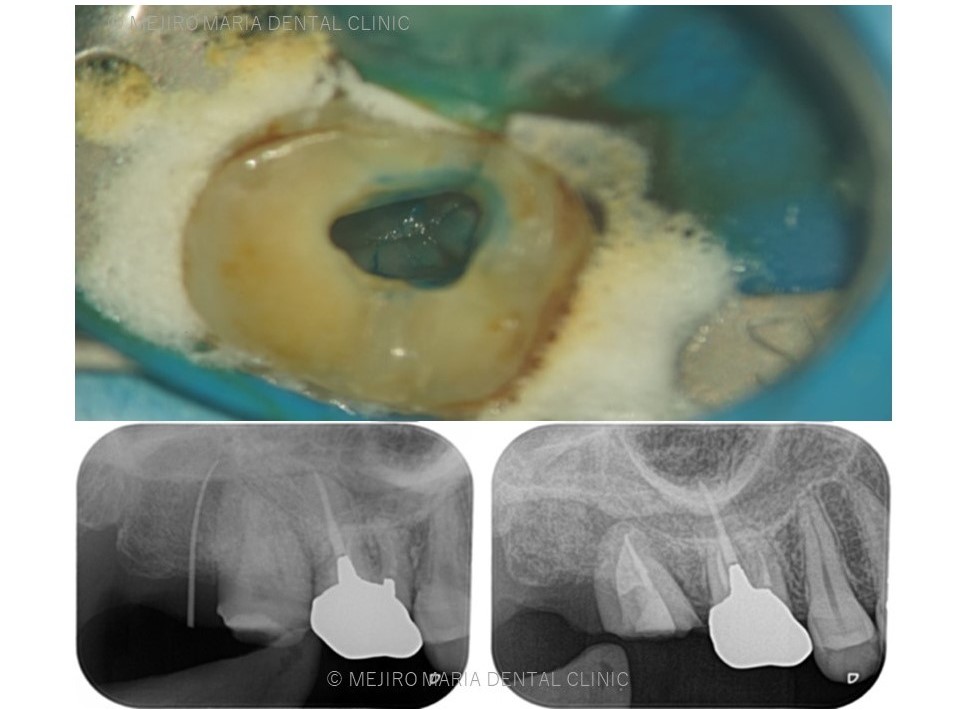

初診時には右上7番に歯髄生活反応は確認できず、歯髄壊死が起因の根尖性歯周炎と診断しました。根管治療を開始するも、歯牙は既に破折しており患者様には抜歯することをおすすめさせていただきました。

左上の親知らずを抜歯後、すぐに右上7番部位に移植を施し2週間経過後に精密根管治療を行いました。

精密根管治療終了後3ヶ月で、術前に確認できた病変の縮小は顕著に確認でき、予後経過は良好と判断します。今後、最終補綴処置に移行し経過観察を行っていきます。

手術後、2週間で移植歯の生着を確認し、通法通りの精密根管治療を施したことで、根尖周囲組織に確認できた病変も3ヶ月後の経過観察では縮小を確認しました。

歯牙移植を行った場合、移植歯の歯髄組織は血流を失うため、歯牙生着を確認後に精度の高い根管治療と定期的な経過観察を行うことが必要になります。